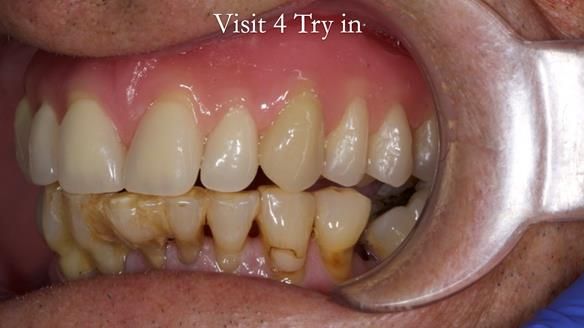

Welcome to my Newsletter 54 showing the making and fitting of dentures (a complete upper metal reinforced denture, a lower immediate partial denture and a definitive Scandinavian designed, metal based lower partial denture) for David, a 75 -year-old man. The full protocol workflow is presented including the use of dentate photographs to mimic his natural teeth.

The clinical situation and treatment process is shown in detail below. I provided the clinical work. Rowan Garstang, my dental technician, provided the technical work.

Interestingly we found that the upper complete denture when finished and fitted didn’t have good enough retention for David’s satisfaction. It was relined by adding compound to the buccal flanges – to almost overextend into the sulcus to ‘create’ a sulcus, followed by using a light bodied silicone impression material. This improved the function of the C/-considerably. A lower Scandinavian hygienically designed lower RPD was also provided which helped with occlusal stability and reseating the upper denture – further improving the fit.